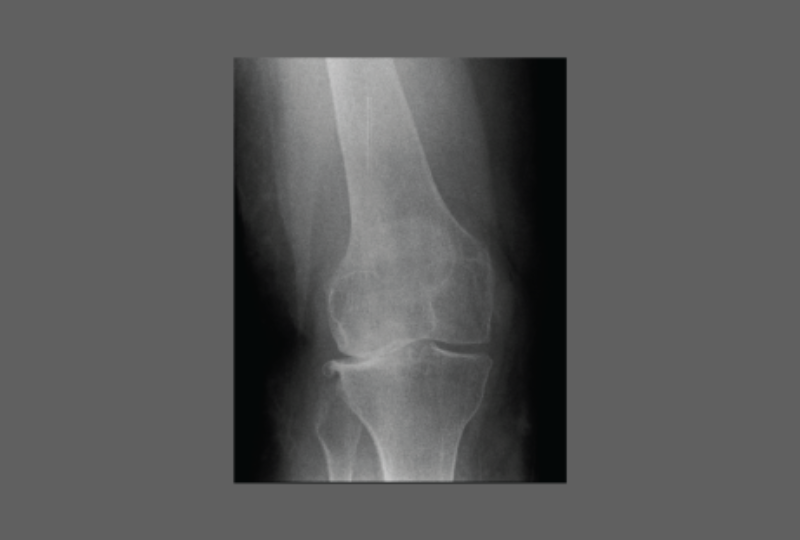

Before Knee Replacement